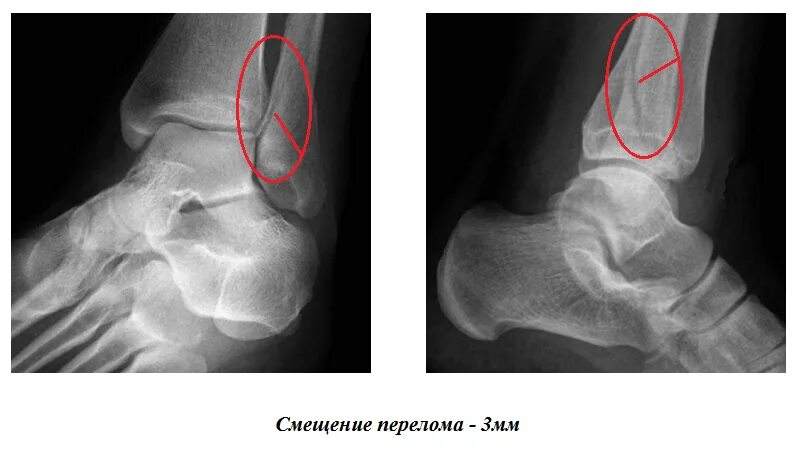

Перелом костей голени код по мкб 10